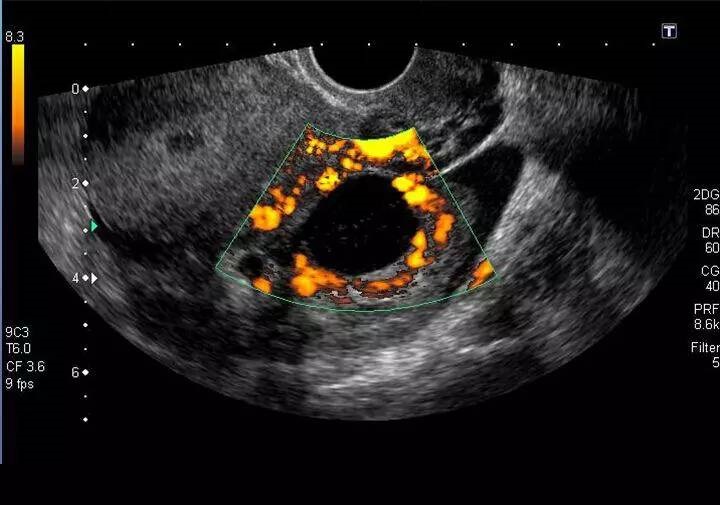

黄体囊肿b超图像

黄体卵巢囊肿